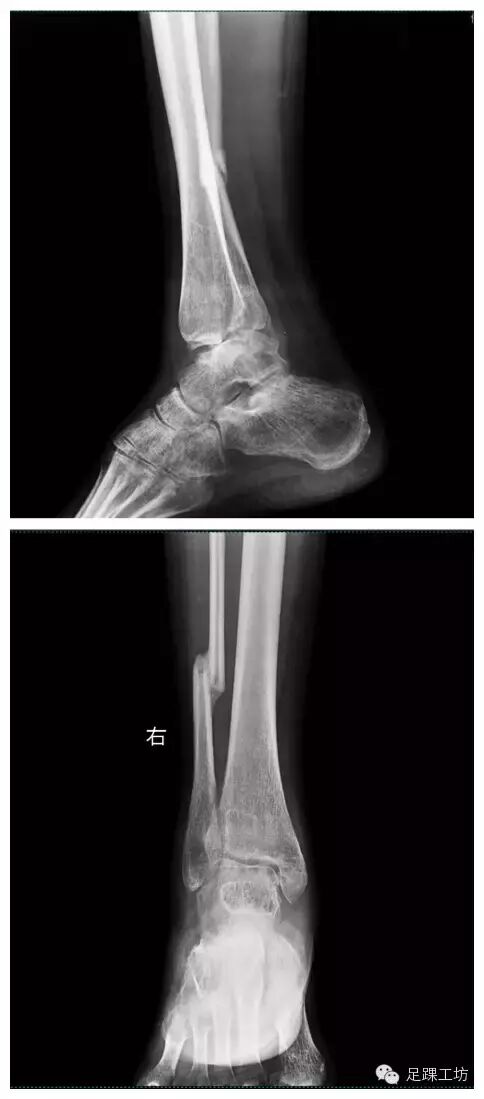

X线

下肢全长X线